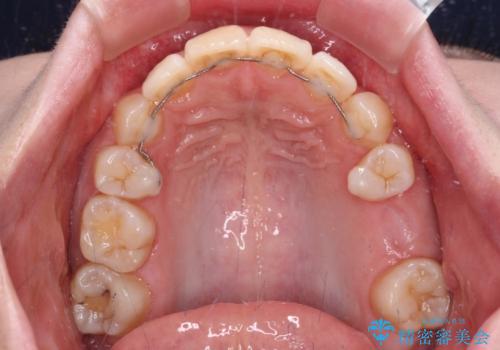

また、上顎臼歯は虫歯により抜歯されてから放置されている状態でした。

舌のトレーニングをしっかりと行っていただきながらワイヤー装置により矯正治療を行い、途中でインプラントを埋入し、矯正治療後に補綴治療を行うこととしました。